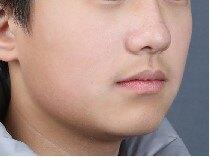

治疗前

11岁小男孩,主诉龅牙,牙齿不整齐。

检查:侧貌突,开唇露齿。上颌前突,下颌后缩,上前牙前突10mm左右,咬合深,咬至上颌粘膜,上下牙弓狭窄,牙列拥挤不齐。